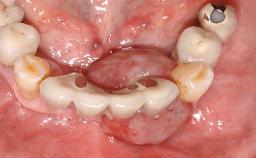

Early (Type 2) placement in a healthy, non-smoking male patient aged 28 years who required removal and replacement of the maxillary right central incisor due to external root resorption. A horizontal bone deficit requires a simultaneous augmentation procedure. The overall esthetic risk is high due to the horizontal bone deficit, medium to high lip line with exposure of the soft tissue margin when smiling, and the patient’s high esthetic expectations.

After flapless tooth extraction and a healing period of 6 weeks, a standard-diameter one-piece implant is placed. A gap between the implant and the facial bone wall is filled with autogenous bone chips harvested from the anterior nasal spine and covered with DBBM particles. Contour augmentation on the facial aspect is achieved using DBBM particles and a collagen membrane, according to the principles of guided bone regeneration (GBR). The flap is coronally repositioned for semisubmerged healing.

Bone Volume Deficient horizontally, allowing simultaneous augumentation